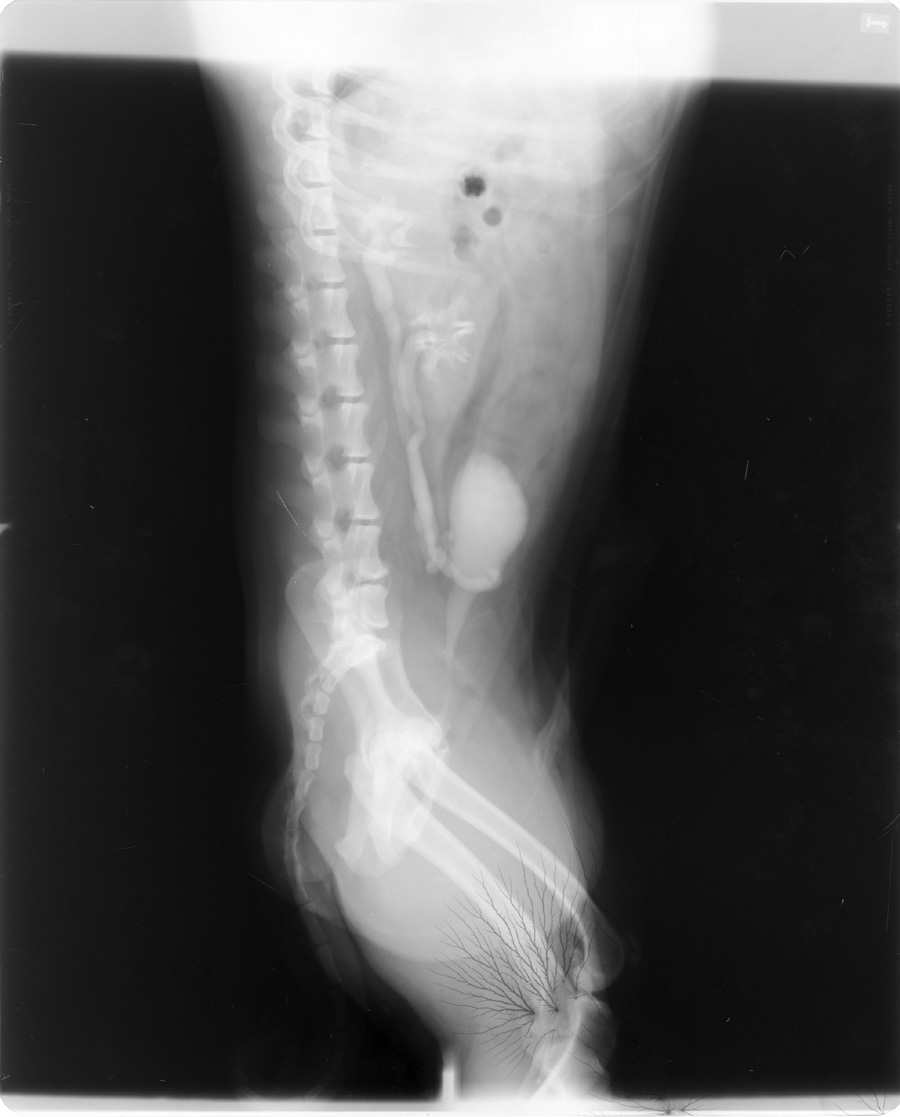

Static causes black branching artifact on the film due to exposure of the film to the elecrical spark of the static discharge.